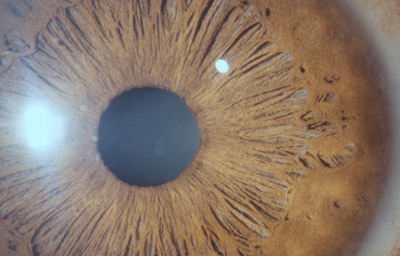

Alrededor del 7º mes la vascularización de la porción mesodérmica del Iris, (estroma iridiano) está llegando a su condición definitiva y el circulo vascular menor se reconoce; la túnica vasculosa lentis ya se ha atrofiado en sus porciones posterior y lateral, e inicia atrofia de su porción anterior (membrana pupilar) afectando en primer lugar su zona central; primero en las arcadas finales del centro los vasos se encogen, pierden circulación y quedan formando pequeñas espirales; el ectodermo iridiano con el esfínter ya se ha profundizado, está a nivel de las segundas arcadas vasculares de la membrana pupilar; cuando progresivamente la segunda arcada se atrofia, la membrana queda separada del margen pupilar y toma la apariencia de 2 capas: una anterior (la membrana pupilar) y otra posterior, el margen de la verdadera pupila. Esa grieta o seudoespacio tiene una extensión muy variable; por lo general, solo se ve en el borde de la pupila, pero puede ocurrir que comprometa la capa superficial de vasos periféricamente. Puede ocurrir que el proceso de atrofia no se detenga en la infancia y continue lentamente a lo largo de la vida, hasta que al final toda la hoja vascular anterior se separe del estroma profundo y quede flotando libre en la cámara anterior unida únicamente en la máxima periferia al estroma iridiano (Iridosquisis).

Lo que generalmente se ve, son parches de atrofia localizados periféricamente al margen pupilar, que toman la apariencia de criptas en el estroma.

El modelado final del Iris adulto, tendrá gran cantidad de variaciones dependientes de la cantidad de atrofia de su hoja anterior y de la pigmentación que desarrolle.

El desarrollo del pigmento en el Iris ocurre después del nacimiento y se define después de los 6 meses. Es de anotar que el esculpido del Iris que se aprecia en los adultos con ojos azules o grises, es debido a la visibilidad de las paredes de los vasos; en los iris muy pigmentados el detalle de la estructura queda oculto.